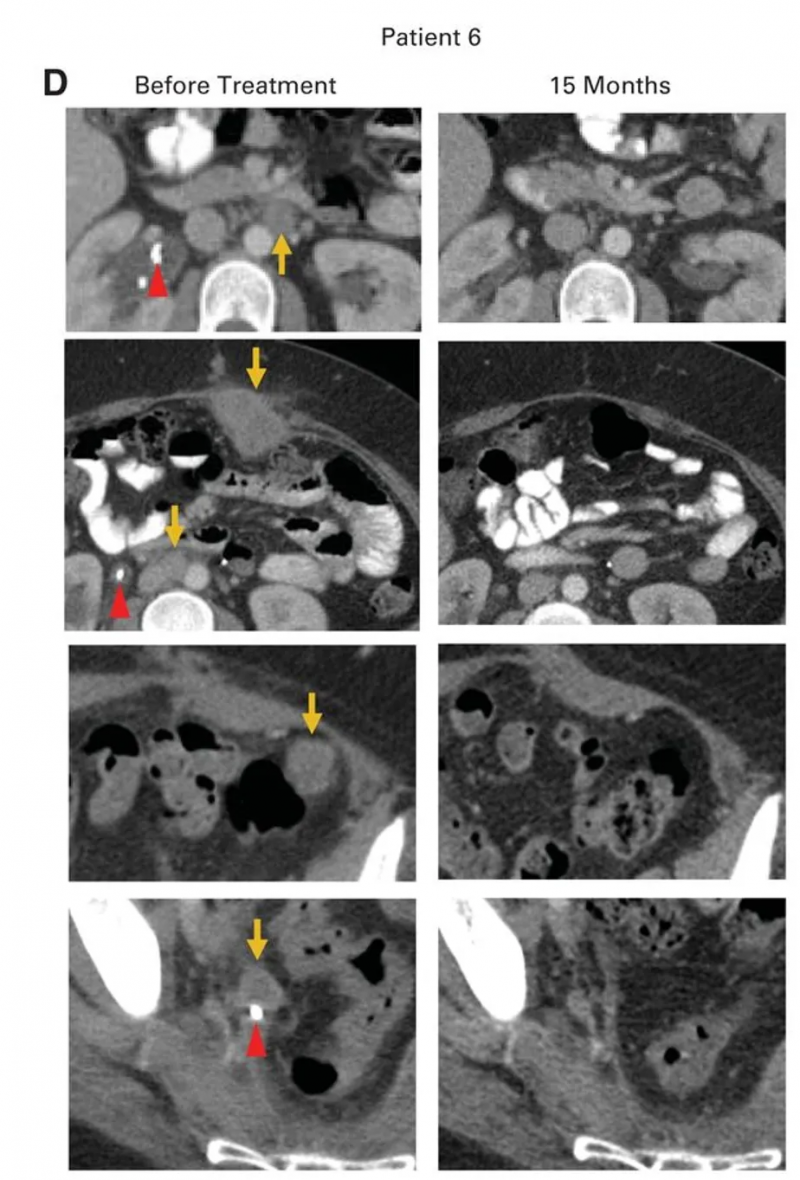

患者6

患者6是一位转移性腺癌女性,原发肿瘤对放化疗耐药,挽救性手术发现腹主动脉旁、髂淋巴结及盆腔其他部位受累,后续癌症进展至腹膜后淋巴结、肝脏表面,伴右侧输尿管肾积水及双侧肺栓塞,需放置输尿管支架并抗凝治疗。治疗时腹膜后、腹壁、结肠旁、肝旁及盆腔均有进展性肿瘤,HPV-TIL治疗后获得完全临床缓解(CR,详见下图B、D),治疗后15个月无疾病复发迹象,右侧输尿管肿瘤消退后已取出输尿管支架。

▲图源“JCO”,版权归原作者所有,如无意中侵犯了知识产权,请联系我们删除